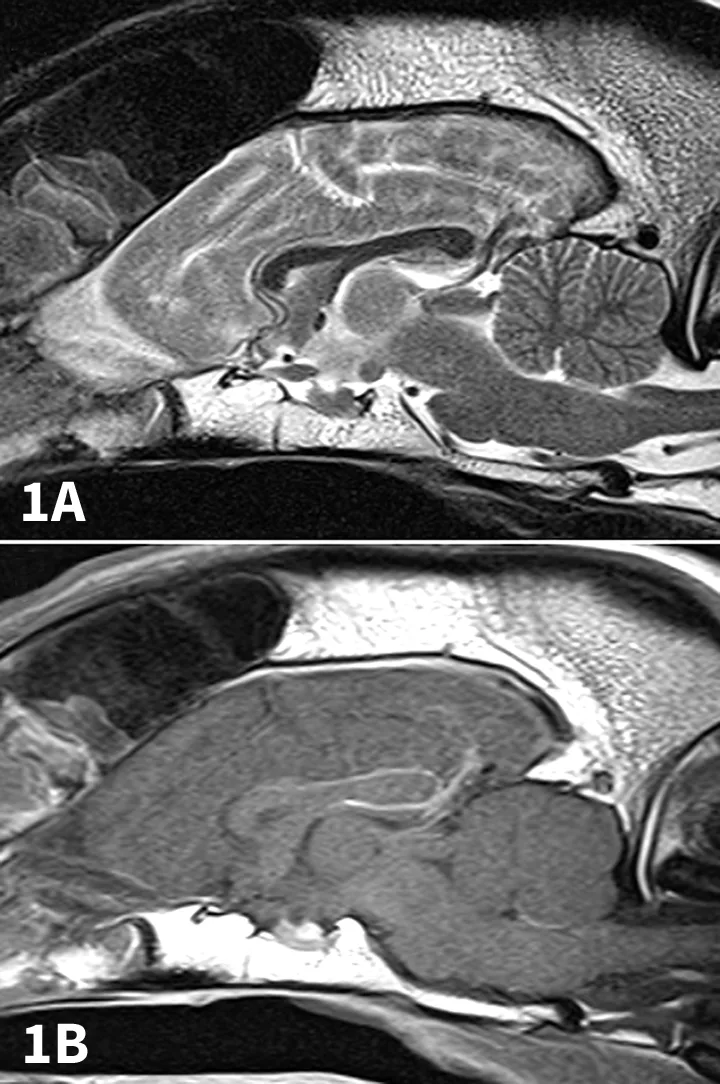

Figure 1

T2-weighted sagittal (A) and contrast-enhanced T1-weighted sagittal (B) MRI scans of a normal dog.

T2-weighted sagittal (A) and contrast-enhanced T1-weighted sagittal (B) MRI scans of a 6-year-old, spayed English springer spaniel dog with CNS neosporosis. The scans depict peripheral atrophy of the cerebellum (especially dorsally) with replacement by CSF (A and B). This finding is consistent with necrotizing cerebellitis. In addition, there is contrast enhancement of the cerebellar nuclei (B). The cerebellum is circled; compare to Figure 1.